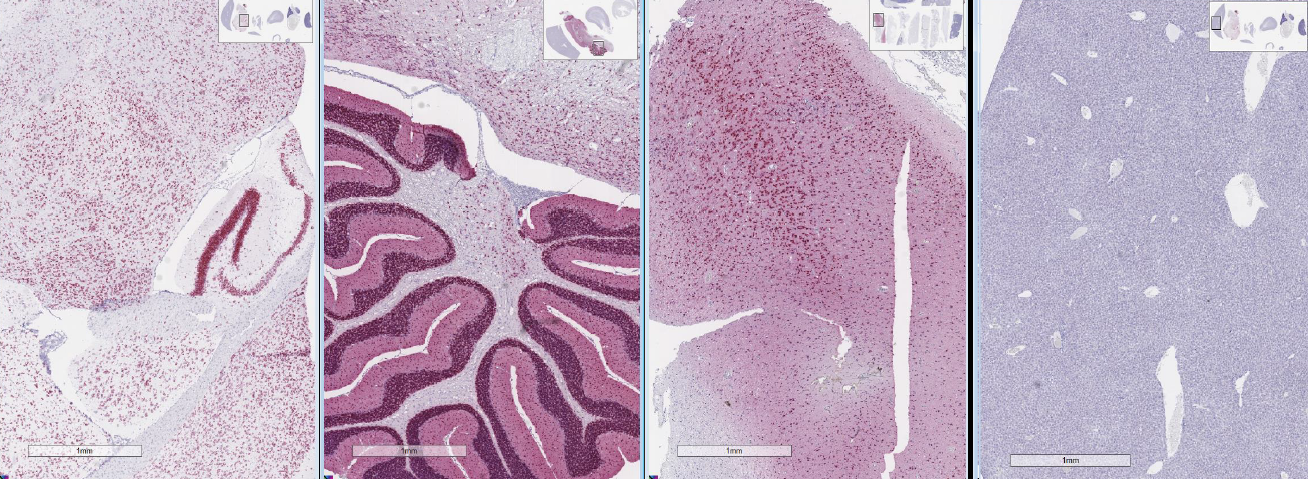

Mouse Brain | Rat Brain | Human Brain

| Mouse liver (NC)

Brain-specific miRNA을 검출하기 위한 miRNAscope assay 실험 결과 |